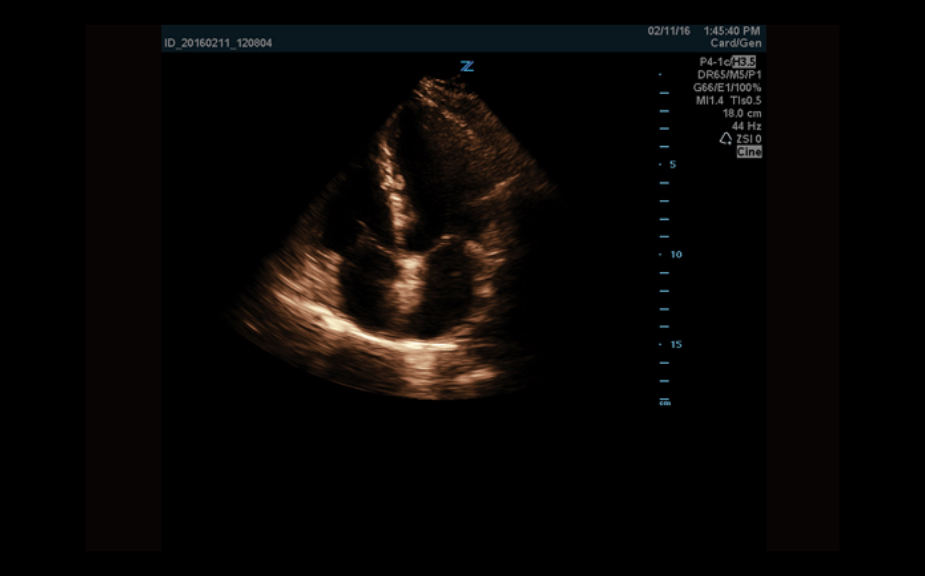

Equipado con software patentado con base en tecnolog├Ła ZONE?Sonography? (ZST),?el Z.One PRO proporciona toma de im├Īgenes Doppler y Modo-B detalladas ├│ptimamente para pacientes, sin importar la complexi├│n del cuerpo, ayudando a asegurar un diagn├│stico confiable.

A trav├®s de una amplia gama de aplicaciones, el Z.One PRO es la soluci├│n de ultrasonido para sus exigentes desaf├Łos cl├Łnicos.

- Insuperable calidad de imagen en todas las aplicaciones

El Z.One PRO est├Ī dise?ado bas├Īndose en ZONE Sonography Technology, una arquitectura de formaci├│n de im├Īgenes innovadora y registrada que adquiere y procesa informaci├│n ac├║stica hasta 10 veces m├Īs r├Īpido que los m├®todos de formaci├│n de haces convencionales.

La plataforma de toma de im├Īgenes por ultrasonido Z.One PRO ofrece una familia completa de transductores de peso ligero que incorporan capacidades de banda ancha extendida y flexibilidad multifrecuencia que proporciona una claridad excepcional y una resoluci├│n de detalle mejorada incluso en las mayores profundidades. El transductor C4-1 puede penetrar a trav├®s del campo de visi├│n mientras mantiene una resoluci├│n espacial y de contraste excepcional.